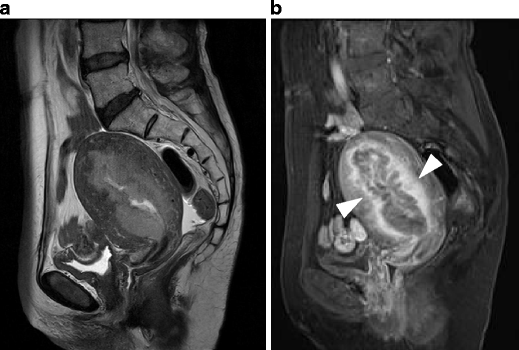

Leiomyosarcoma in a 60-year-old woman. a Sagittal T2-weighted image demonstrates an irregular-shaped large mass of heterogeneous intensity in the posterior wall of the uterus (arrows). b Postcontrast T1-weighted images with fat suppression demonstrate multifocal, unenhanced areas of necrosis within the tumor

Endometrial stromal sarcoma in a 47-year-old woman. a Sagittal T2-weighted image demonstrates an ill-defined lesion of slightly increased intensity in the posterior myometrium of the uterus (arrows). Note the bands of low signal intensity within the lesion, which represent preserved myometrial bundles amidst the infiltrating nests of tumors cells. b Fusion image with DWI onto T2-weighted image reveals increased signal corresponding to the infiltration tumor in the myometrium